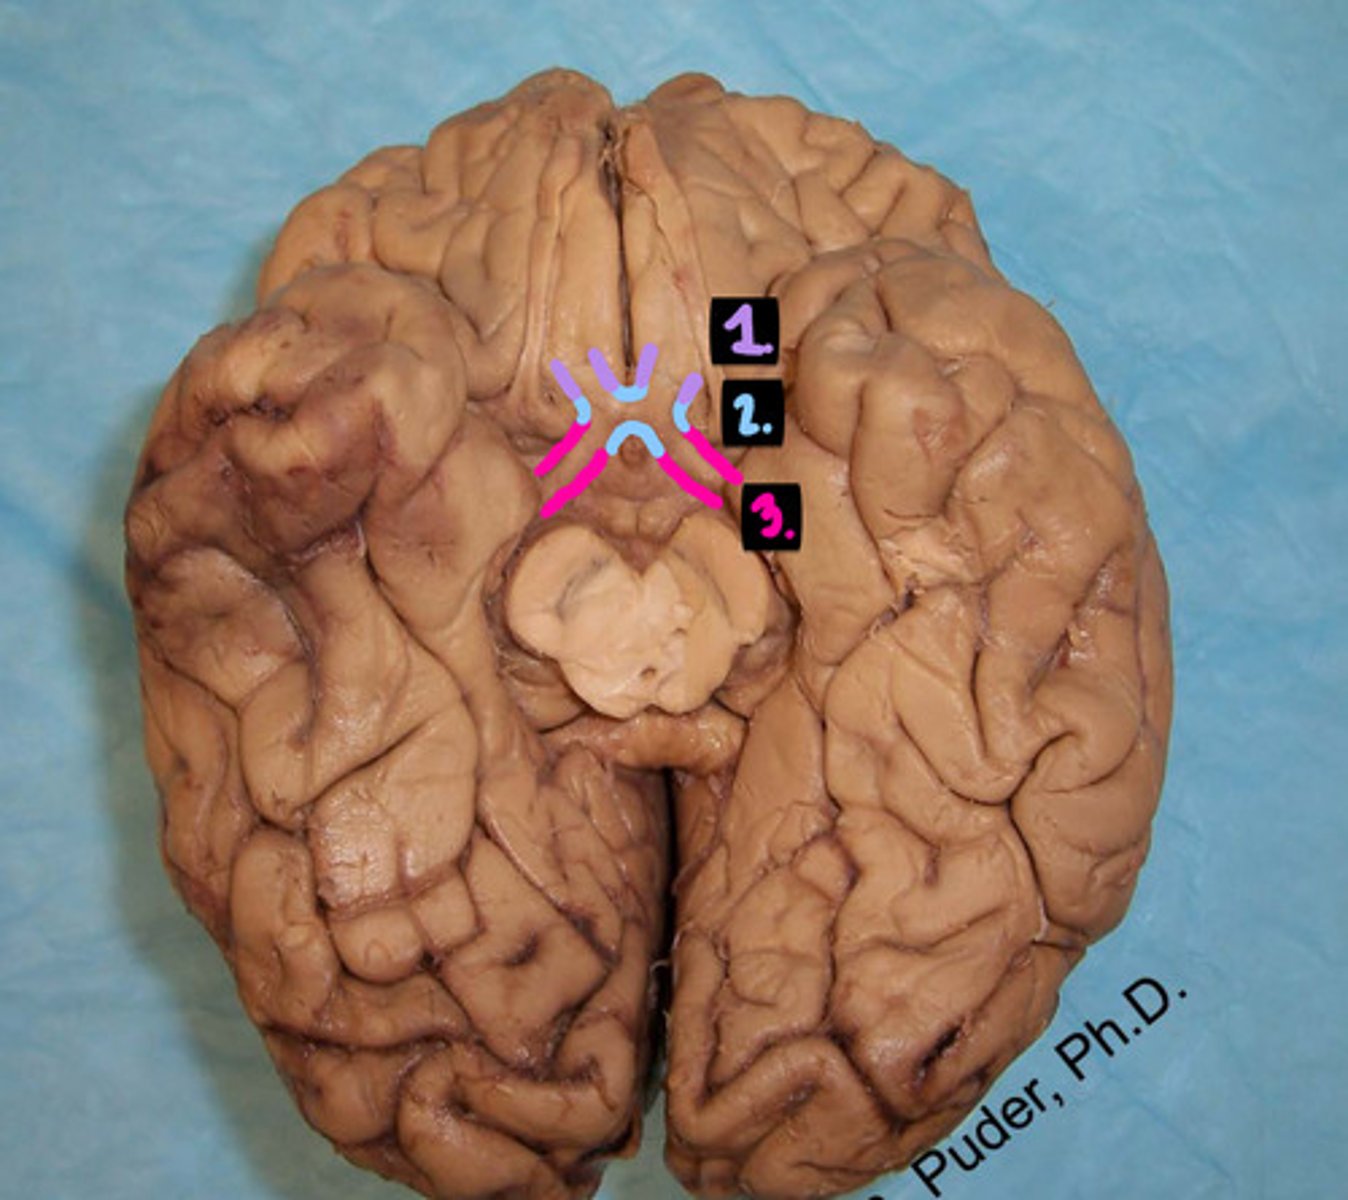

1. optic nerve

2. optic chiasm

3. optic tract

label